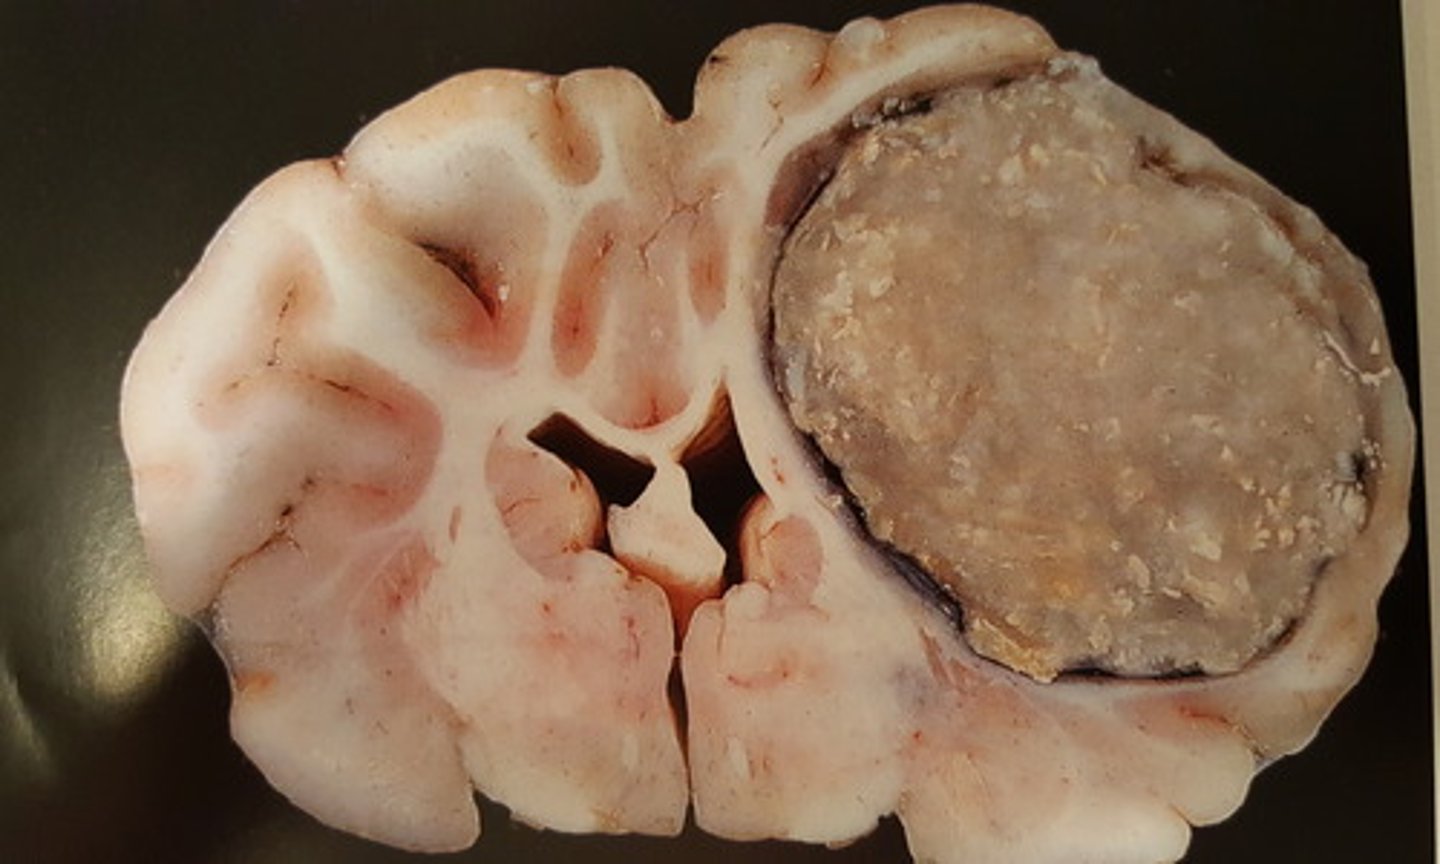

oligodendrogliom, benign neoplasi

Hjerne fra okse. Patoanatomisk diagnose?